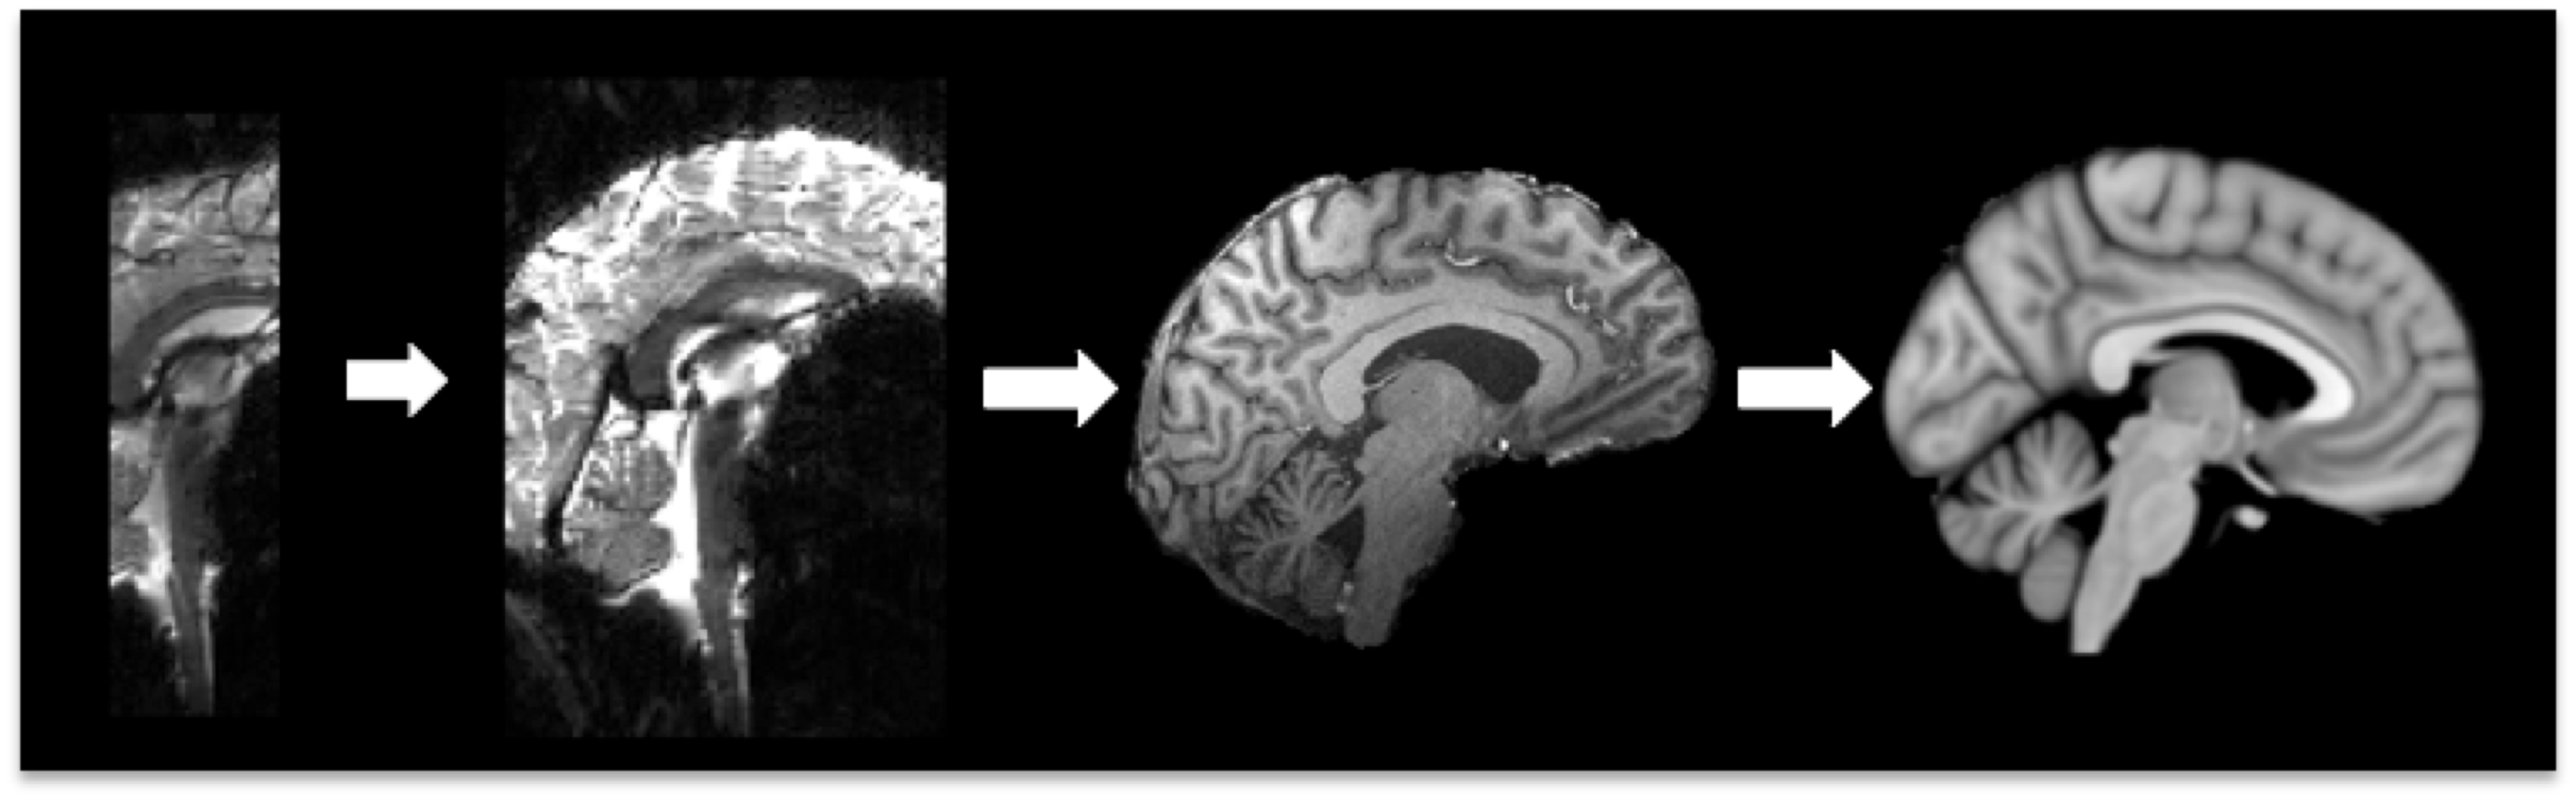

Example result: Two-stage registration - EPI (functional) to T1 Structural to Standard Space

Example of Two Stage Registration